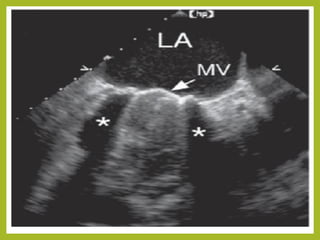

A transesophageal echocardiogram was performed on a patient who presented

with evidence of endocarditis.

In panel A, a large, echo-free space (∗) is noted between the aortic root and the left

atrium. The arrow identifies an area of communication between the left ventricular

outflow tract and this echo-free space.

In panel B, color Doppler imaging confirms flow through this space. This represents

a large abscess, an ominous complication of bacterial endocarditis